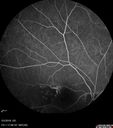

Coats Disease - Parafoveal Telangiectasis Type I - Right Eye402 views67 year old man with long history of vision loss in the right eye. Previously treated with laser, avastin. VA 20/200.Feb 11, 2020

Coats Disease - Parafoveal Telangiectasis Type I - Right Eye393 views67 year old man with long history of vision loss in the right eye. Previously treated with laser, avastin. VA 20/200.Feb 11, 2020

Coats Disease - Parafoveal Telangiectasis Type I - Right Eye370 views67 year old man with long history of vision loss in the right eye. Previously treated with laser, avastin. VA 20/200.Feb 11, 2020

Coats Disease - Parafoveal Telangiectasis Type I - Right Eye394 views67 year old man with long history of vision loss in the right eye. Previously treated with laser, avastin. VA 20/200.Feb 11, 2020